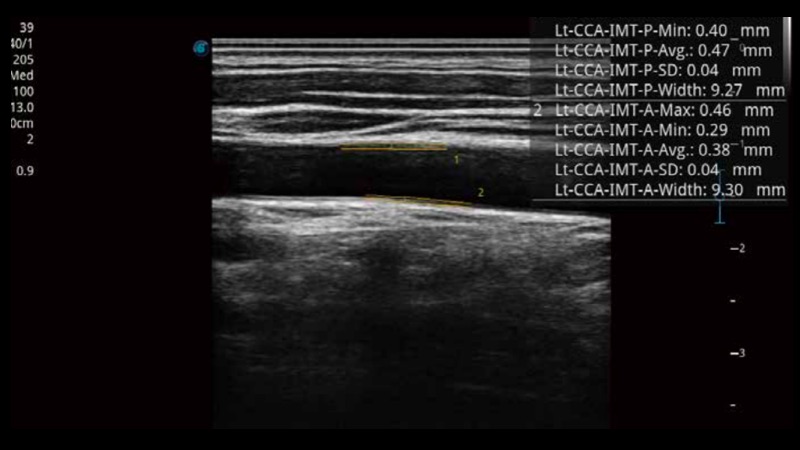

自動識別前后壁內膜厚度,為心血管疾病早期評估提供快速準確依據。